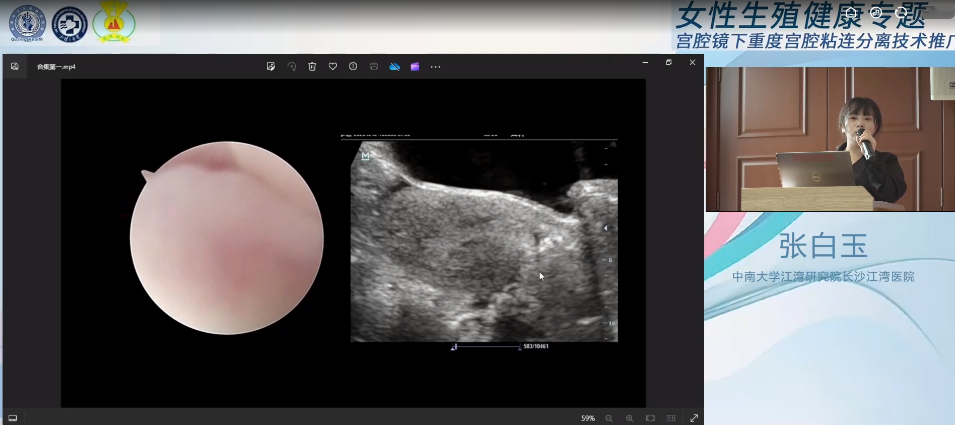

会议分为宫腔镜手术演示和主题授课两部分进行,首先由徐大宝教授搭档我院超声影像科张白玉副主任演示了多台精彩的宫腔镜手术。在张白玉3D超声技术无创、精准的术中引导下,徐大宝教授成功为两位患者顺利分离了粘连,恢复了正常宫腔形态,为患者后续生育带来了极大的希望。

在随后环节中,张白玉副主任带来《宫腔手术术中超声监护策略》的主题授课。她介绍,术中超声是指手术过程中采用超声技术辅助手术医师诊治疾病的方法,目前实时腹部超声监护已经成为妇科宫腔镜手术监护的首选方法,具有便利、可重复性好的优势,与宫腔镜手术联合,无腹部创口,创伤小、不破坏盆底结构,能减少手术并发症并提高手术更快好孕。通过授课,张白玉将术前精准诊断宫腔粘连、术中超声经验和诸多前沿技术倾囊相授,与会人员纷纷表示受益匪浅。